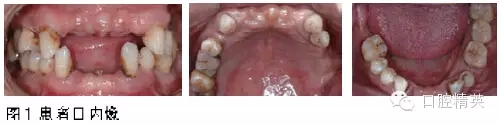

口腔衛(wèi)生狀況差,菌斑、軟垢大量,牙石(+~++),煙斑大量。全口牙齦緣略暗紅,探質(zhì)軟,牙周袋(PD)2~9mm,出血指數(shù)(BI)2~4,附著喪失(AL)2~8mm。余牙咬合不穩(wěn)定,雙側(cè)顳下頜關(guān)節(jié)未見(jiàn)明顯異常。

11、12、14、21、22、25、26、27、28、31、32、35、41、42、47、48缺失,剩余牙槽嵴較豐滿。13、15、16、17、18、23、24、33、34、36、37松動(dòng)Ⅰ~Ⅲ°。PD 5~9mm。38、46松動(dòng)Ⅰ°,PD3~6mm,根分叉病變Ⅰ~Ⅱ°。43松動(dòng)Ⅰ°,PD2~4mm,過(guò)長(zhǎng)。44、45頰面楔狀缺損,無(wú)松動(dòng),PD2~3mm。